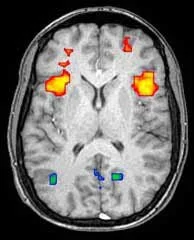

​Once images are acquired, processing and analysis can be accomplished using a variety of software packages.  Some of these software systems are freely distributed by the research community whereas other regulatory approved software products designed for clinical application are available from commercial vendors.   In general, these fMRI analysis software programs perform two functions.   First, the raw fMRI images are preprocessed in an effort to correct for such factors as patient head motion, slice timing differences, and various sources of image noise or artifact.  In the research setting, preprocessing may include alignment of the images to a common anatomic space or atlas.   The second major analysis task is derivation of the statistical maps which form the fMRI “images”.   This is accomplished by voxel-wise statistical comparison of T2* signal in the brain images acquired during stimuli presentation with those obtained during absence of the stimuli.   A variety of statistical methodologies have been advocated including the general linear model, correlation analysis, or simple voxel wise t-tests.  The final output is a map that shows voxels in which stimulus related brain activation is considered to be statistically significant based on a specified threshold such as a p-value, t-value or z-score with the chosen measure depending on the specific statistical model employed.   For neurocognitive research applications, it is common to employ a uniform, fixed statistical threshold such as p=0.001 across all subjects as well as some form of correction for multiple comparisons.   However, given inter-individual variability in cerebrovascular responsiveness, the statistical threshold generally requires customization for clinical work in single patients.